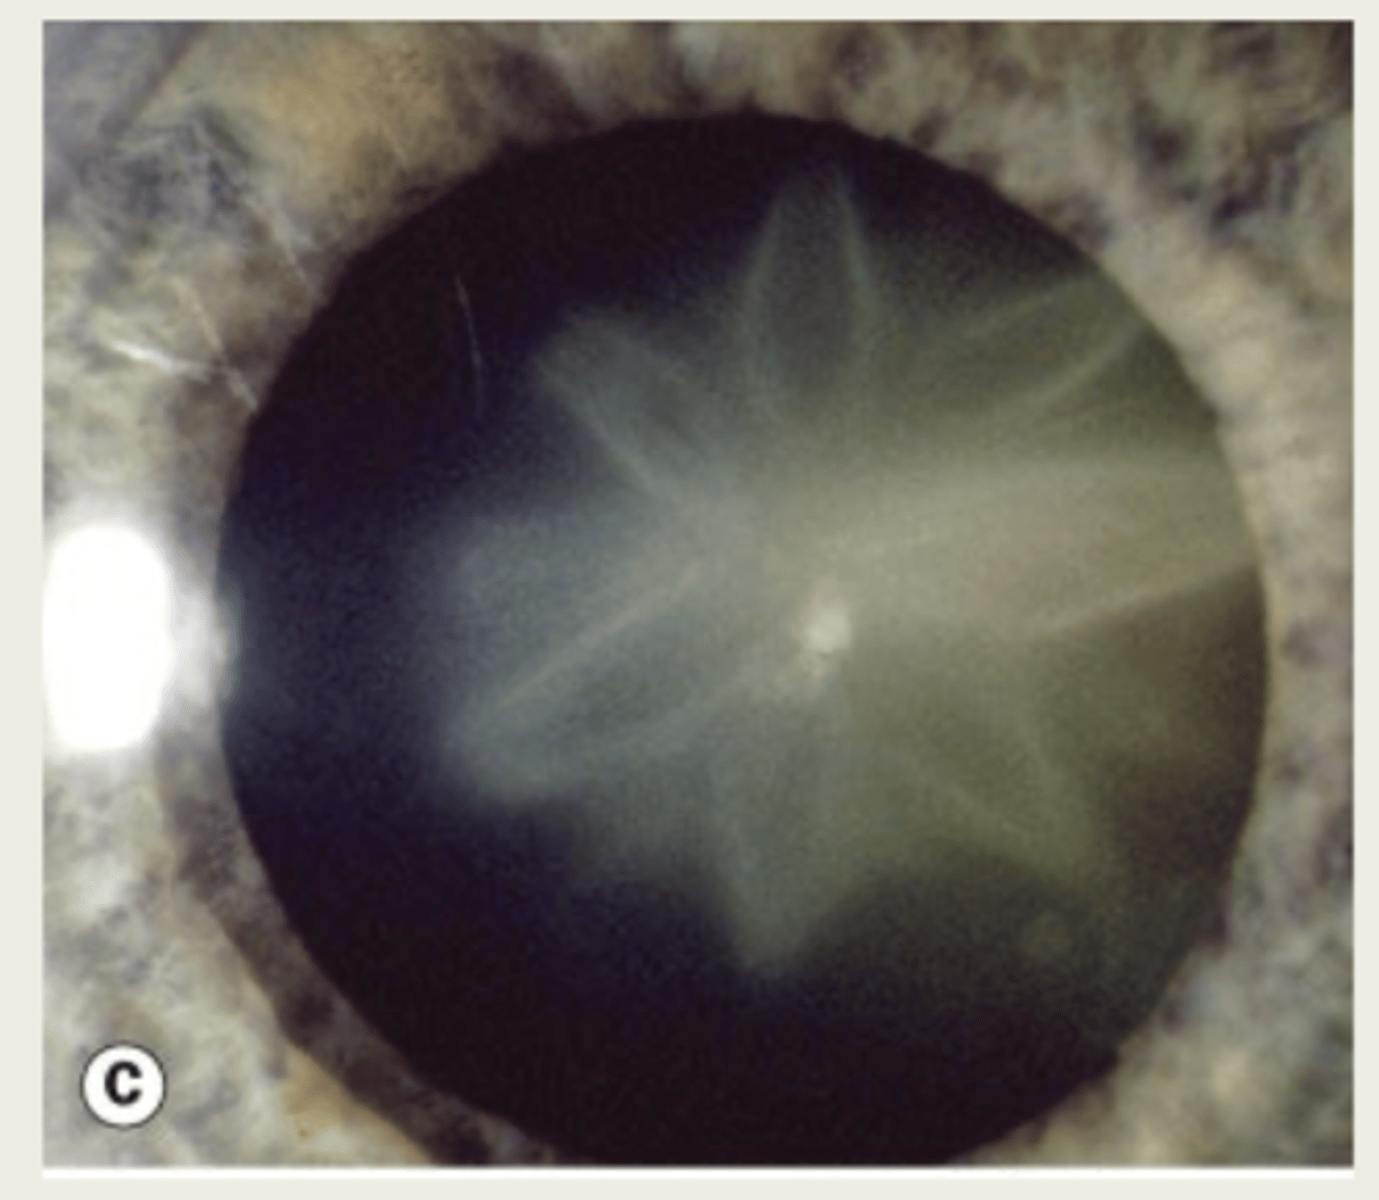

What is the presentation of a christmas tree cataract?

polychromic (many colors) crystals in cortex - crystals will morph into stellate cataract

What are the polychromic crystals of christmas tree cataracts composed of?

1. cholesterol

2. lipids

3. calcium